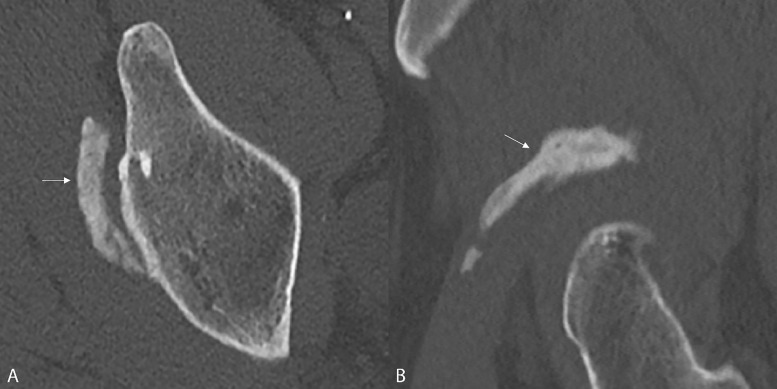

教学要点:正确诊断股直肌间接头异位骨化的线索是其位于髋臼边缘上方及其(倒置的)逗号状形态。

Teaching point: The clues to the correct diagnosis of heterotopic ossification of the indirect head of the rectus femoris are its location above the acetabular rim and its (inverted) comma‑like morphology.